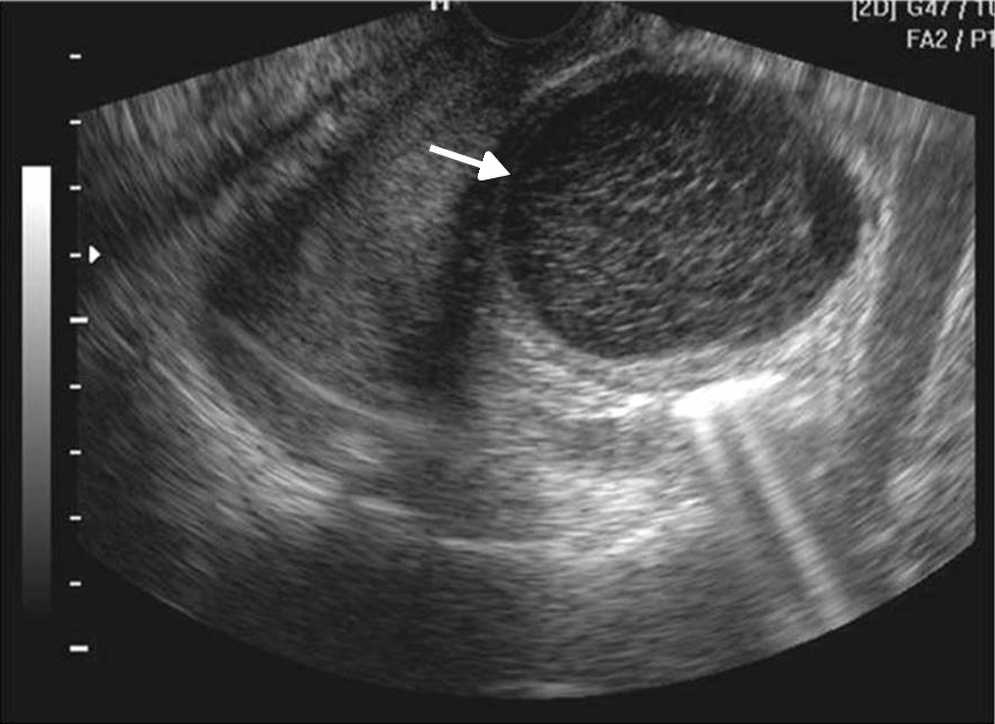

Las principales causas de esta dolencia son los quistes de ovario simples o hemorr??gicos, los embarazos ect??picos, las enfermedades inflamatorias pelvianas, las torsiones de ovario y otras patolog??as, muchas de las cuales tienen caracter??sticas ecogr??ficas propias que permiten su diagn??stico5 (figs. 1-3).

La ecograf??a determina la naturaleza s??lida o qu??stica de las masas anexiales, la presencia de septos o elementos s??lidos, y su vascularizaci??n con la exploraci??n Doppler (fig. 4). Estos hallazgos ayudan a determinar la benignidad o malignidad de la masa5,10.